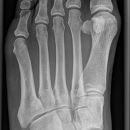

Fuß schräg

Komplexe anatomische Verhältnisse => Zusätzlich a.p.- und evtl. noch streng-seitliche Aufnahme oder Vergleichsaufnahmen der Gegenseite anfertigen! Komplexen Luxationen/ Frakturen => großzügige CT-Indikation! Zentrale Kalkaneusfrakturen (vgl. Kalkaneus) => CT-Indikation! Isolierte Frakturen des Os naviculare, der Ossa cuneiforma oder des Cuboids sind Raritäten => Immer nach zusätzlichen Verletzungen (Calcaneus, Talus, OSG,...) suchen!

Beurteilungskriterien

- Gelenkspalten der Fußwurzelgelenke und Mittelfußes frei einsehbar? Gelenkspaltweiten zwischen den Fußwurzelknochen und Tarsometatarsalgelenken < 2,5mm

- Korrekte Stellung, kongruente Gelenkflächen?

- Mittelfußknochen II – V frei projiziert, gleichmäßige Abstände?

- "target areas" subtiler Frakturen: Talushals, Proc.posterior tali, Proc.lateralis tali, Proc.ant.calcanei, Sustentaculum, Entenschnabelfraktur (knöcherner Ausriß des Ansatzes der Achilllessehne), Tuberositas ossis metatarsalis V!!!

Cave:

- akzessorische Knochen und Normvarianten der Apophsenentwicklung Wachstumsalter (vgl. a.p.-Aufnahme)

- Ermüdungsfrakturen initial oft nicht erkennbar => Röntgenkontrolle in 8-10d.